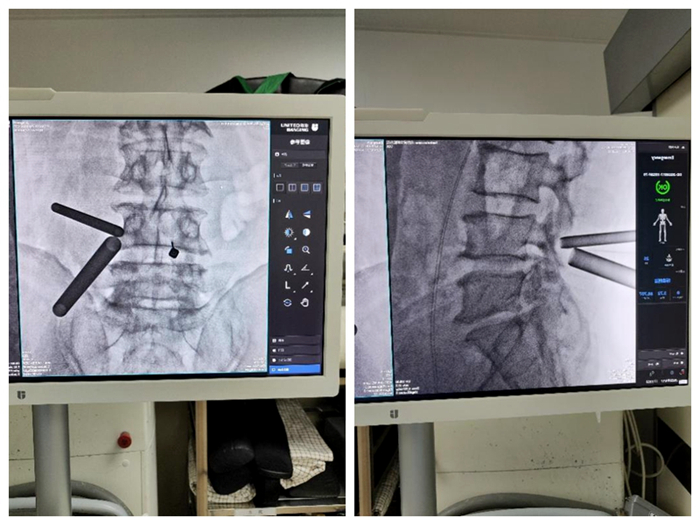

术中定位

来就诊的患者大都是长期饱受腰腿痛的折磨,已经严重影响了正常的行走坐立,生活质量严重下降,多方求医尝试了很多治疗方法仍未得到明显好转和根除。我院脊柱外科团队仔细研究每位患者病情,针对每位患者制订个性化治疗方案,选择利用国内较为前沿的新型脊柱微创技术——微创双通道内镜技术(UBE技术)为病人解决难题。脊柱外科团队在完善术前必要检查的前提下,制订了详尽完备的术前规划,分别为患者实施了UBE下椎管扩大减压手术,改术式仅通过2个1cm的小切口便完成了神经减压操作,出血量不到50ml,术后患者腰腿痛症状明显消除,恢复理想,患者及家属对手术疗效非常满意。